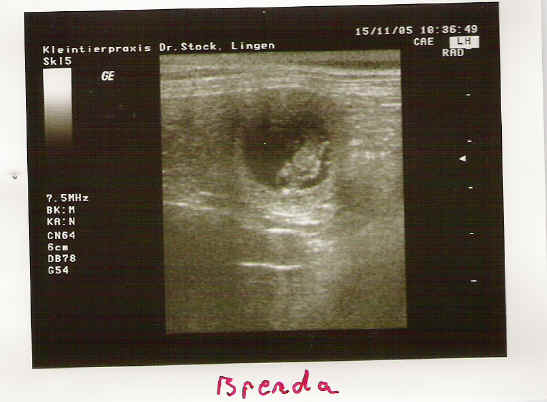

Neue US - Aufnahmen vom 31. Tag der Tragzeit von Brenda v. Weinbacher Land.

Eine Hündin trägt ca.63 Tage, mal mehr, mal weniger. Unsere Hündin hat sich den 64. Tag ausgesucht. Nach 5 -6 Wochen kann man der Hündin sehr gut ansehen, dass Sie tragend ist, denn der Bauchumfang hat stark zugenommen und das Gesäuge ist stark abgeschwollen. Hier sieht man eine Hündin mit einer Tragzeit von 50 Tagen. Vom rechten Horn ist nur der zum Geburtsweg führende Teil dargestellt.